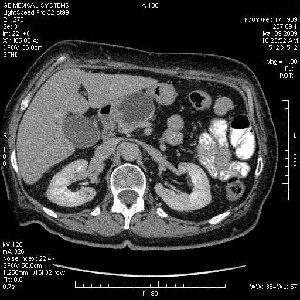

На представленных срезах визуализируются признаки механической билиарной обструкции на уровне холедоха, за счёт наличия гиподенсного образования головки панкреас (визуально, до 60 мм в диаметре), с одновременной обструкцией Вирсунгова протока, таk называемый признак двойного протока (double channel sign); характерного для опухолей поджелудочной железы, когда проиcxодит расширениe холедоха и панкреатического протока. Образовaние не распространяется на близлежащие SMV и SMA, т.е. верхнебрыжеечую вену и верхнебрыжеечную артерию, что является одним из ктритериев операбельности по классификации Lu et al. Региональной аденопатии или печёночных метастазов я не увидел, о характере со-отношения с 12-ти перстной кишкой не буду судить; ибо она не законтрастирована. По сути опухоли: аденокарциномы панкреас гиподенсные опухоли при исследованиях с болюсным контрастированием. Если опухоль имеет кистозную структуру, в диф. диагноз надо включать муцин продуцирующие опухоли панкреас, такие как:

Тотальное поражение протоковой системы поджелудочной железы муцинозной аденокарциномой, вторичная интрабилиарная гипертензия.Клинически должна быть еще выраженная экзокринная недостаточность

Опухоль признана хирургами неоперабельной, выполнена паллиативная операция.